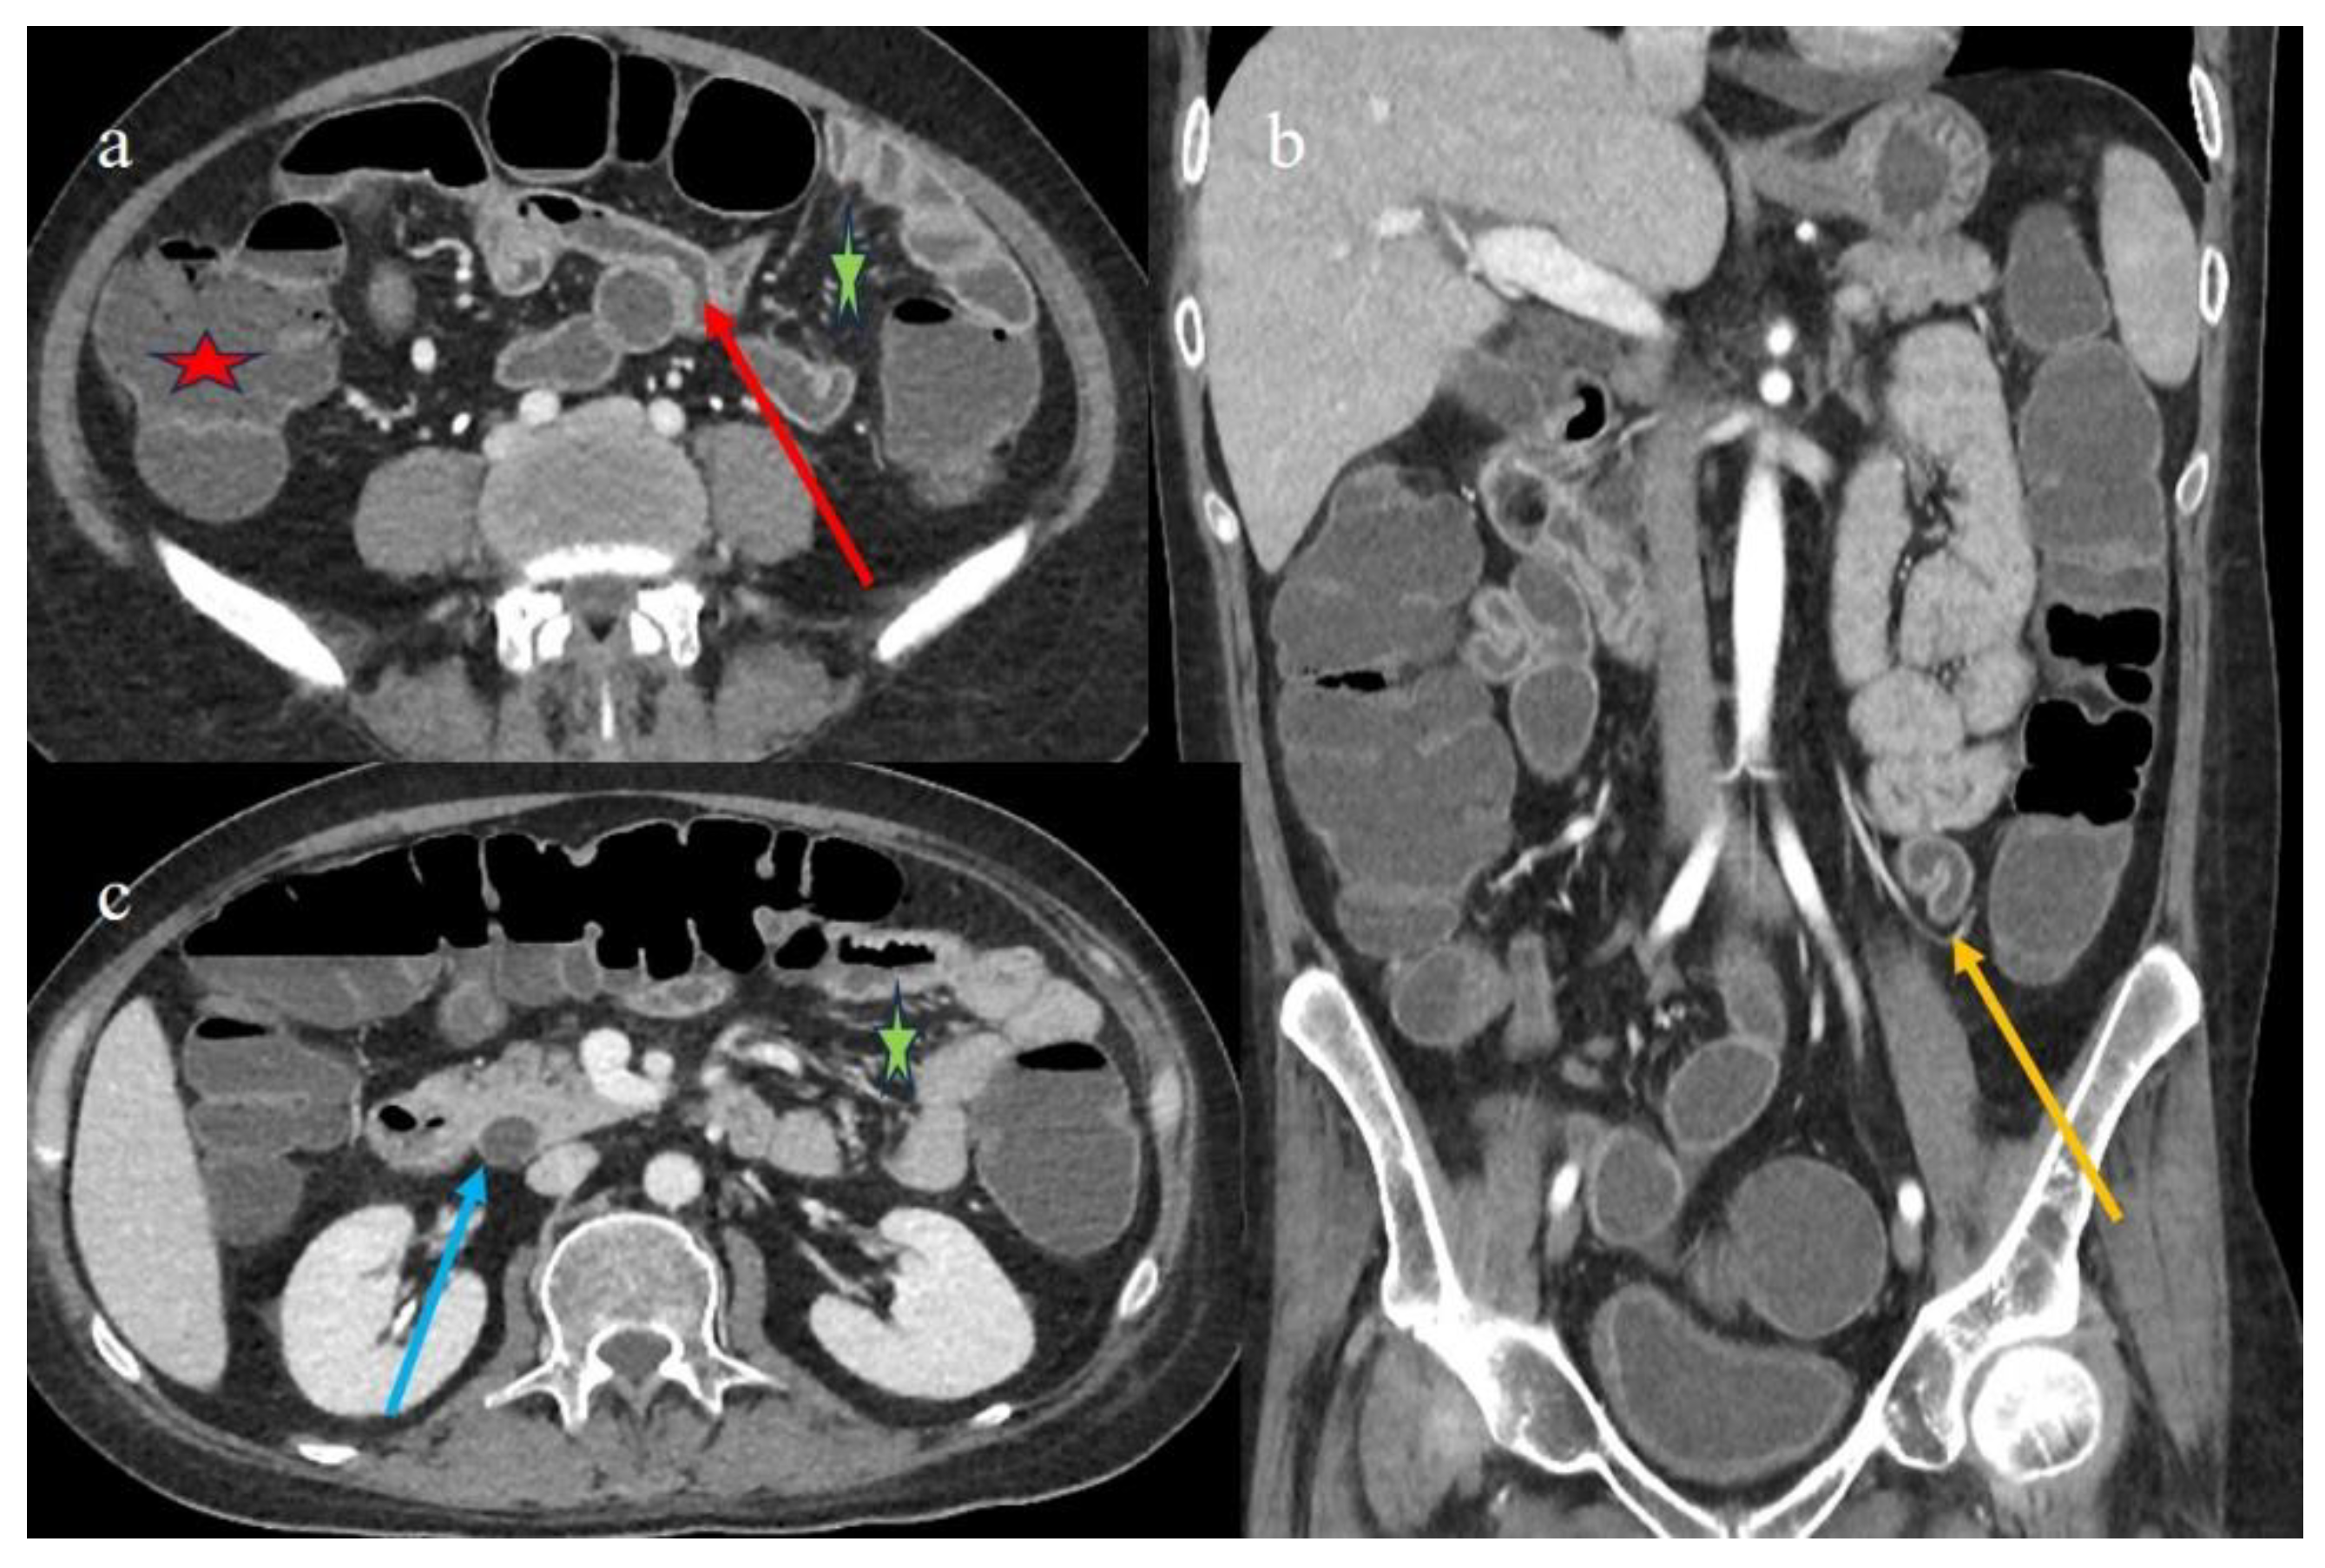

| 1 | P | P | Multisegmental and plurifocal parietal thickness with homogeneous mucosal enhancement on distal ileus | Multisegmental thickness with homogeneous mucosal enhancement | Mild diffuse comb sign and poor reactive mesenteric lymph node | Splenic infarct |